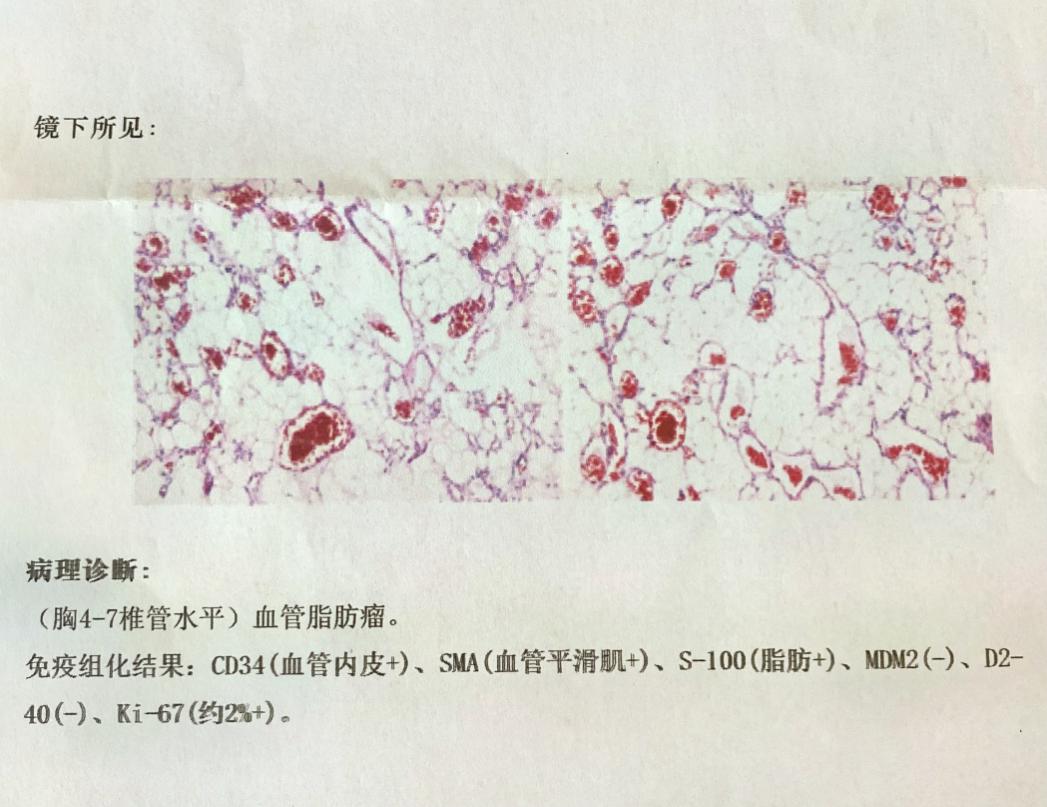

主任白西民、副主任姚胜及支部书记党俊涛组织全科室人员讨论手术及围手术期治疗方案后,4月21日,由副主任医师冯毅主刀、主治医师赵云洁协助全麻下成功切除肿瘤。手术操作在显微镜下进行,真正实现了切口小、出血少、脊髓继发损伤轻微的手术预期。术后患者清醒并返回病房,即感双足僵硬感消失,足趾灵活性较术前明显改善,术后病理报告胸椎管内血管脂肪瘤。经科室医务人员精心治疗及护理后患者肌力逐渐恢复并好转出院。